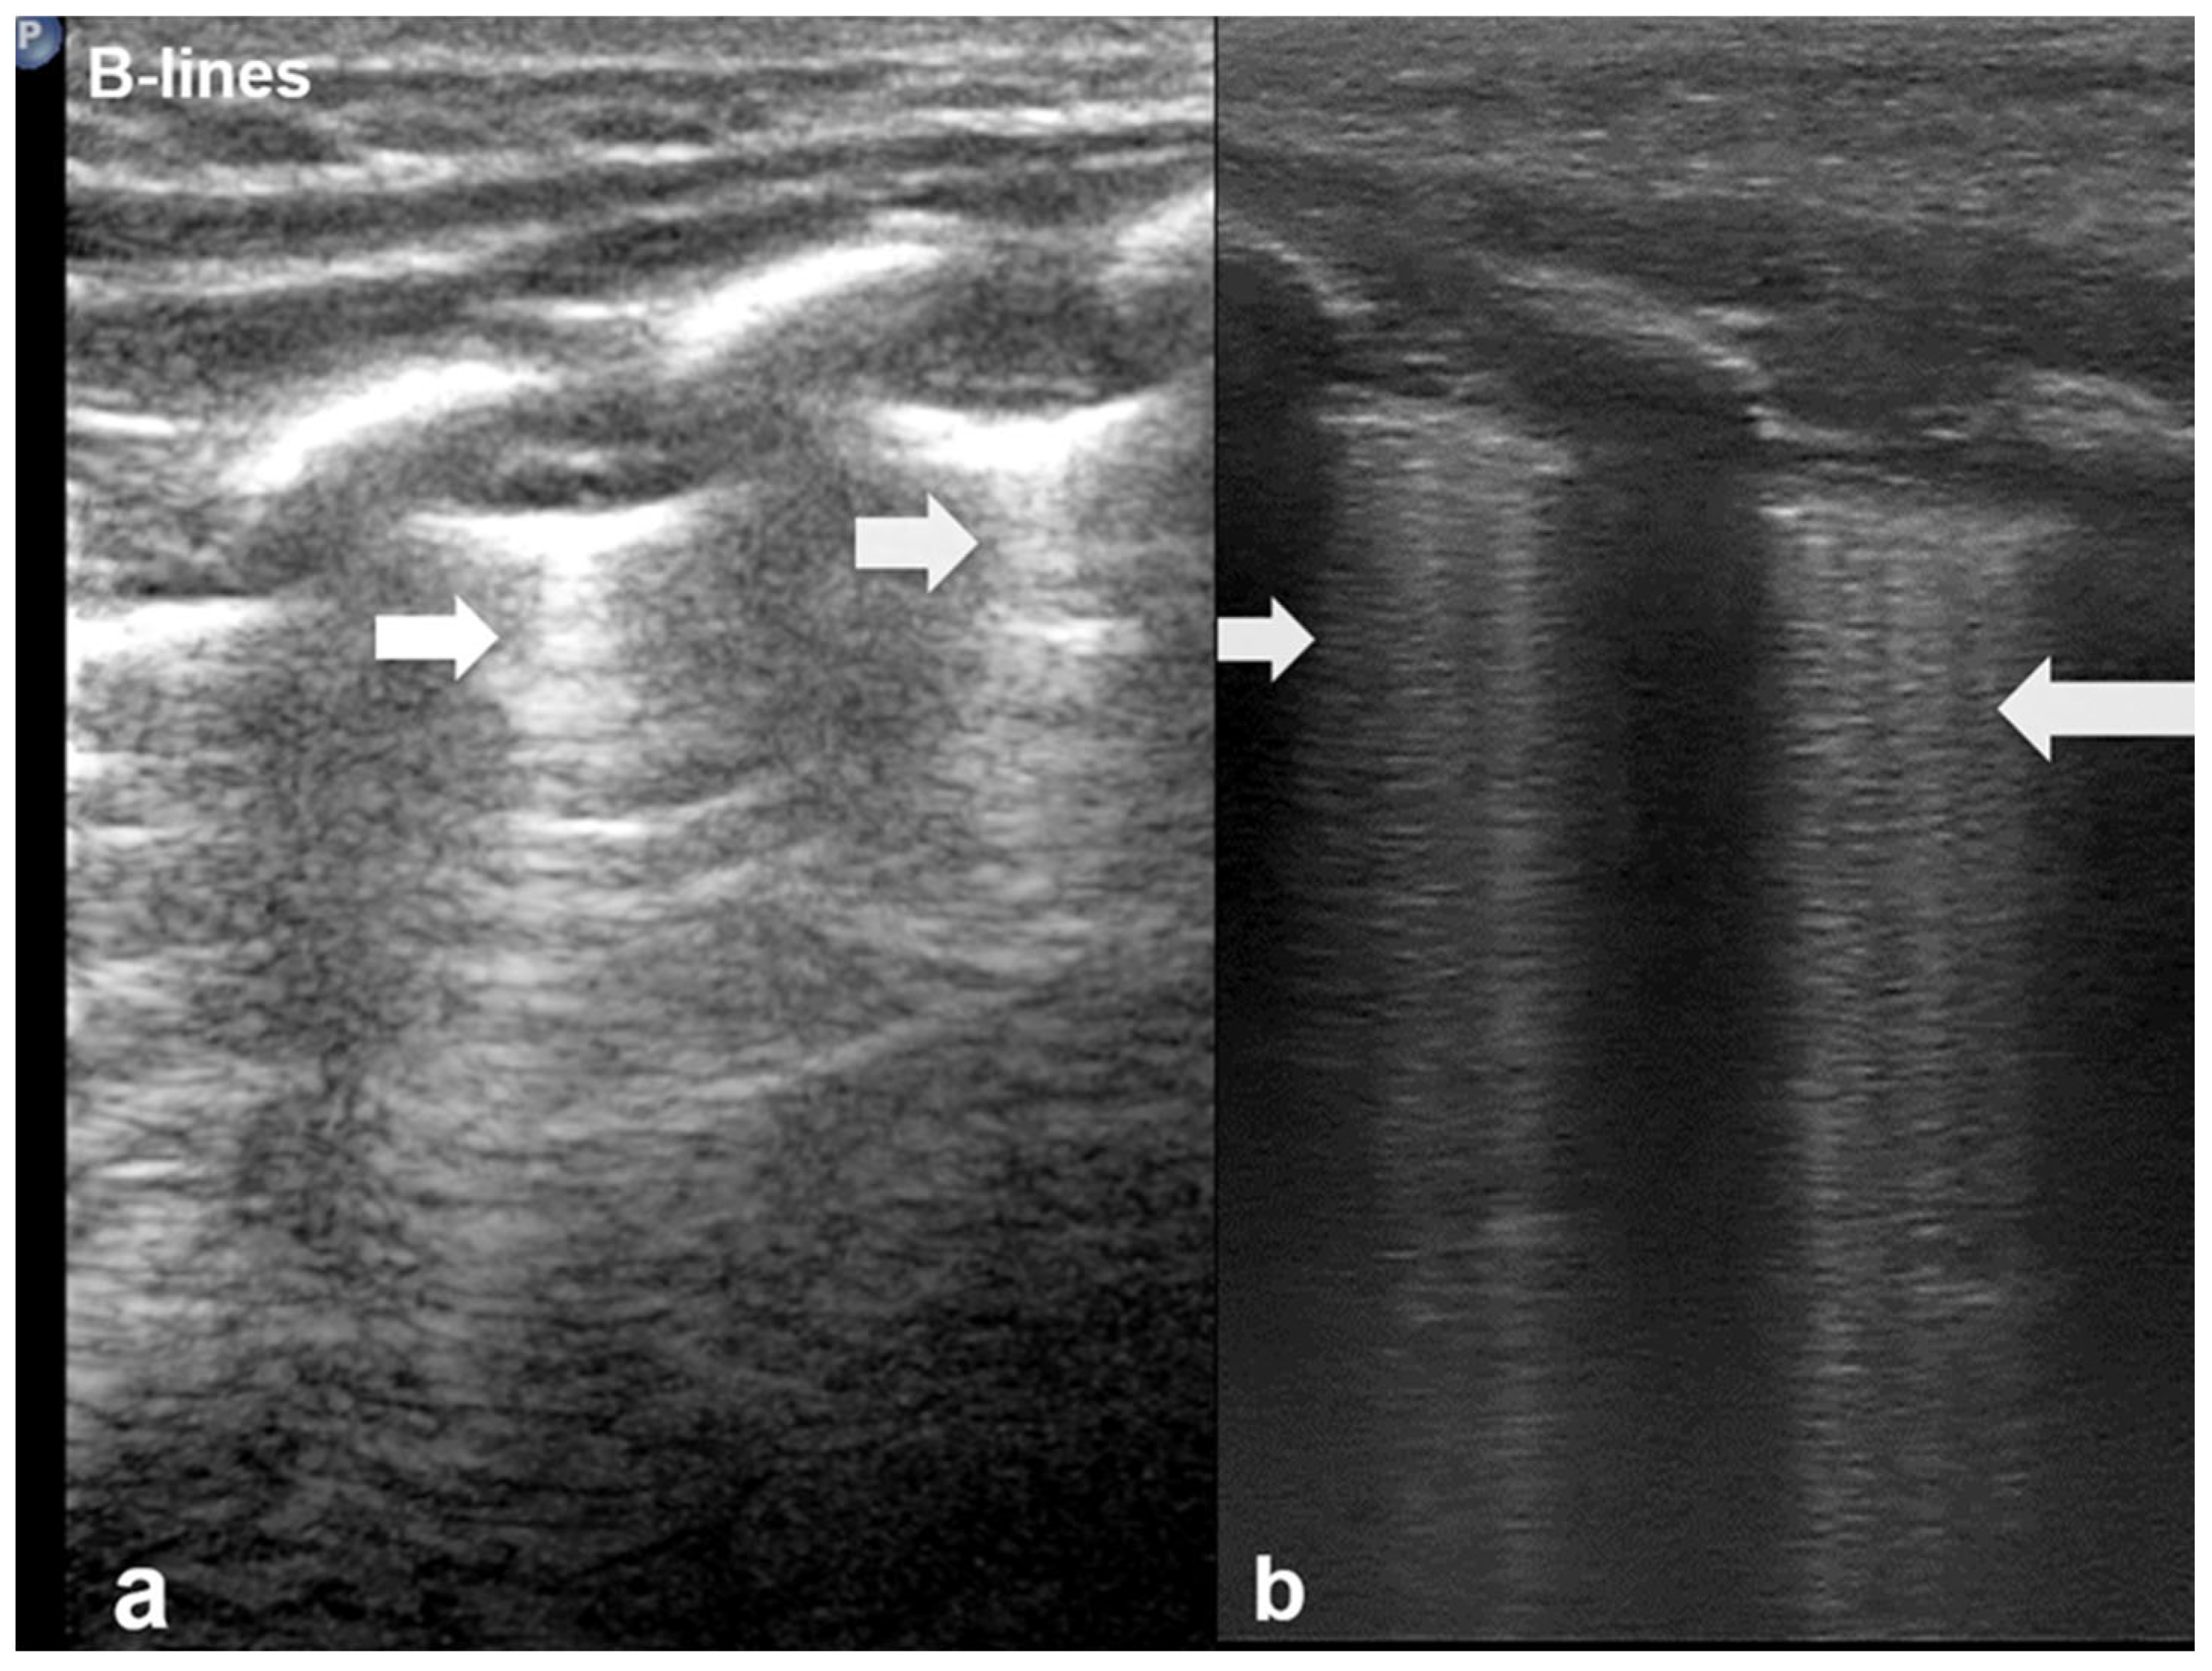

B-lines are vertical reverberation-like hyperechoic artifacts seen during LUS imaging which originate from the pleural line and extend to the bottom of the imaging field without fading in intensity (Figure 2a). B-line artifacts move in synchrony with lung sliding and intersect horizontal A-lines, effectively obscuring them. Their presence is typically associated with fluid accumulation in the alveoli or interstitial space, and they are commonly referred to as ultrasound lung comets. However, B-lines are frequently observed in neonates and can appear as a normal finding within the first 24 to 48 h after birth [13,14,17]. During LUS imaging, identification of up to two B-lines at the lung base is considered to be normal, while the presence of three or more B-lines between the intercostal space in a single view is considered significant and indicative of an underlying pathology. If multiple B-lines are identified by LUS, then the patient likely suffers from interstitial syndrome. When the air content in the lungs decreases, the number of lines tends to increase, because of the associated increase in lung density. Moreover, when the identified B-lines are confluent, this is an indication that the alveoli are filled with sub-pleural fluid. When interstitial edema is present, the presence or absence of B-lines can guide the administration of fluids [16,17,18,19]. However, it should be noted that B-lines are absent in the aforementioned pneumothorax.

Figure 2.

B-lines: Vertical reverberation-like hyperechoic artifacts originate from the pleural line and extend to the bottom of the image (a). This artifact could be normal (<3 in an intercostal space) or abnormal when are more than three, multiple or coalescent B-lines (b).

According to severity of the lung or interstitial pathology, B-lines may be solitary, few, multiple or even coalescent (Figure 2b), resulting in three imaging patterns associated with increasing severity: black lung, black and white lung, or white lung (Figure 3) [20,21].